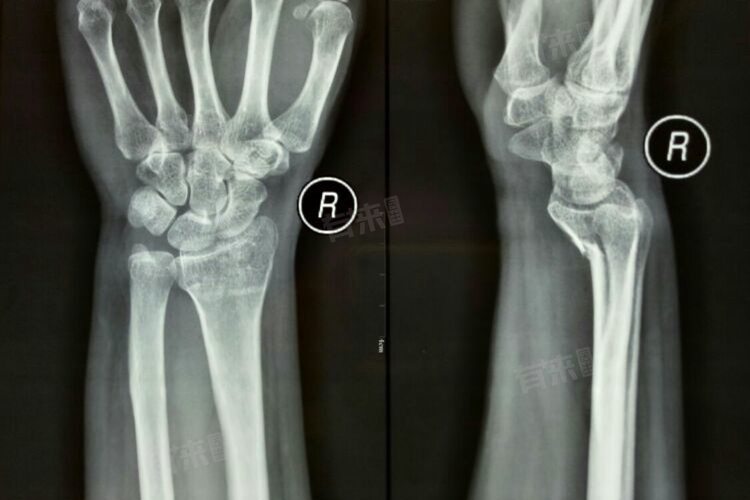

- Smith骨折多为跌倒时腕关节屈曲、手背着地受伤引起,主要表现为腕部疼痛、肿胀,可出现银叉样畸形,但与Colles骨折的畸形方向相反。患者应积极就医进行检查、治疗,可以改善预后,检查后患者应积极遵医嘱进行相关治疗。

- Smith骨折通常是可以治愈的,对于轻度的Smith骨折,没有明显移位的情况下,可以采用保守治疗,如手法复位后石膏或夹板固定。一般经过一段时间的固定和康复,骨折部位可以逐渐愈合,恢复腕关节的功能。

- 如果骨折较为严重,出现明显移位、粉碎性骨折或者合并其他损伤时,可能需要手术治疗。手术可以更准确地复位骨折,使用内固定装置如钢板、螺钉等固定骨折部位,为骨折愈合创造良好的条件。术后经过规范的康复训练,大多数患者也可以获得较好的恢复效果。